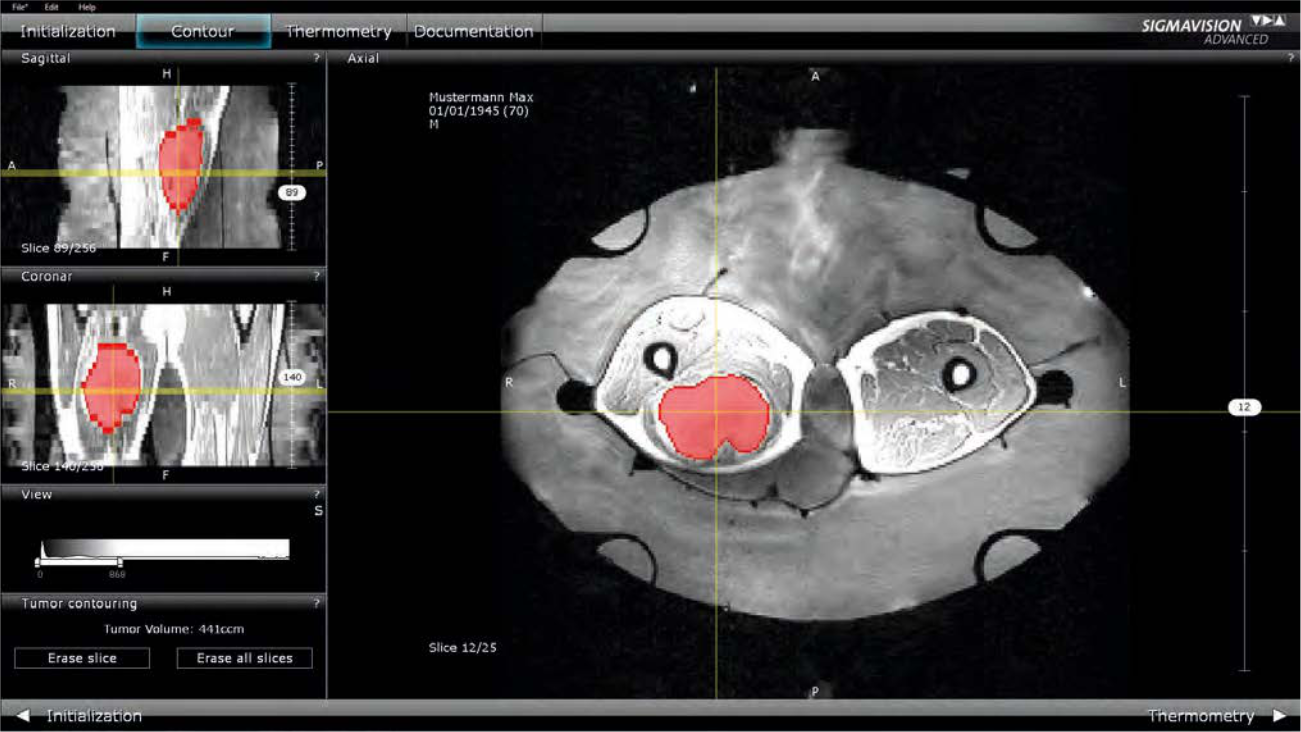

Efficient Tumor Contouring in 3D

The tumor can be contoured in SIGMAVISION ADVANCED for evaluation.

- Thanks to the three-dimensional MRI images, SIGMAVISION ADVANCED enables 3D editing of the contours.

- The axial, sagittal, and coronal slices of the MRI images are displayed on the screen.